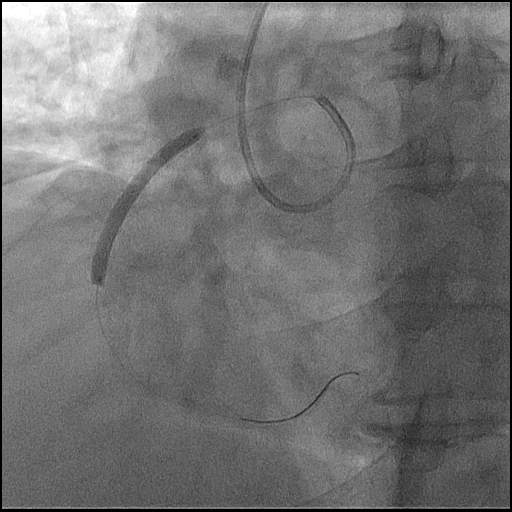

Coronary angiography has been performed, right coronary artery couldn't be find in the right coronary ostium, with EBU 3.5 right coronary artery was visualized arising from the left coronary ostium. LAD was occluded and RCA was with 99% stenosis in mid segment.

Diagnostic angiography has been performed and occluded Left Anterior descending artery was visualized but, the right coronary artery couldn't be find from the right coronary ostium. 6F EBU 3.5 catheter trough the right radial approach has been inserted and we could visualize right coronary artery arising from the left coronary ostia. Direct stenting was performed with 3.5/38mm DES at 17 atm. After this procedure we continued to LAD, passed the occlusion with BMW wire after which predilatation with 2.5/20 mmx 14 atm has been performed and after that 3.0/28mm DES at 15atm was implanted with good end result